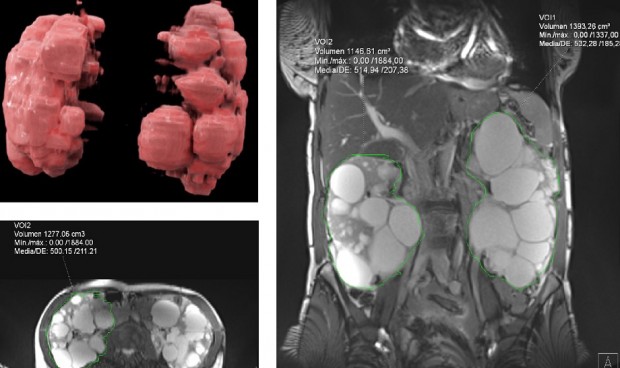

Resona, el centro de diagnóstico por imagen avanzada del grupo Asisa, ha incluido en su cartera de servicios la cuantificación de volumetría renal mediante resonancia en equipo de tres teslas en sus estudios sobre poliquistosis renal. Esta técnica mejora la capacidad de diagnóstico de la enfermedad renal garantizando la máxima seguridad de los pacientes.

La aplicación de esta técnica permite a Resona ofrecer estudios más precisos sobre la evolución de los pacientes y mejorar la eficacia de los tratamientos. Actualmente, el volumen renal total (VRT) en el seguimiento de pacientes con poliquistosis renal autosómica dominante se considera un biomarcador de progresión a insuficiencia renal y, por lo tanto, un factor determinante a la hora de realizar el pronóstico sobre la evolución de la enfermedad.

La cuantificación de volumetría renal mediante resonancia en equipo de tres teslas mejora la capacidad respecto a otros medios de diagnóstico, como el uso de la ecografía y el cálculo del volumen mediante la fórmula elipsoide, que ofrece datos menos precisos y menos reproducibles. En el caso del cálculo volumétrico mediante TAC, aunque es una técnica más exacta que la ecografía, implica el uso de radiación ionizante.

La resonancia magnética de tres teslas con la que cuenta Resona, utilizando la segmentación renal a través de inteligencia artificial y planimetría, ofrece cálculos del VRT más precisos, sin irradiación y reproducibles, además de permitir el estudio adicional de la patología renal y la complicación de los quistes, su crecimiento o presencia de hemorragia, así como obtener imágenes 3D.